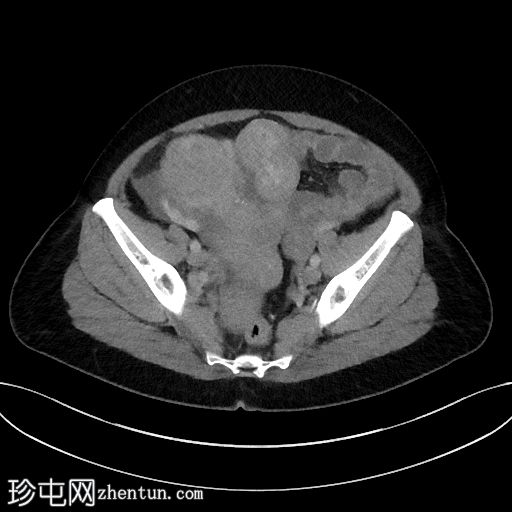

6个月前CT检查

CT

2.jpg

既往CT显示子宫内有多发性肌瘤,但在子宫右侧一个较大的肌瘤内可见一处不典型、中心低密度区。

无腹水。